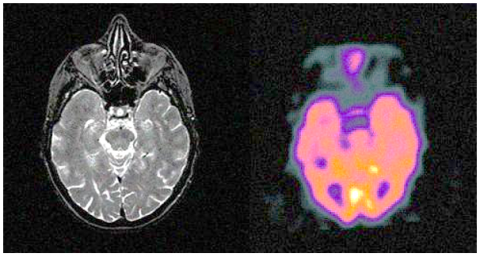

Today, medical imaging plays an essential role in clinical diagnosis and treatment. CT images, for example, are widely used in fractures because they can record bone condition. MRI scans can be used to diagnose brain diseases such as brain tumors and the like. CBF (Cerebral Blood Flow) images can objectively reflect changes in the tension and tension of cerebral arteries. SPECT images can measure the biological activity of cells and molecules. However, these images have limitations that may limit their use in real applications. Single-photon emission computed tomography (SPECT) images, for example, cannot be clear enough to absorb brain structures. Therefore, SPECT images are always used with computed tomography (CT) or MRI images for clinical diagnosis. Finally Medical images (http://www.med.harvard.edu/AANLIB/home.html) were captured by the SEWT method [13].

In Figure 2, examples of such images are shown as input images. There are four images in each row, with the first two images being the same as the input images and the second two images being noisy images with a standard deviation value of 10.

(a). Input images

(b). Noisy images with $\sigma=10$

(c). Input images

(d). Noisy images with $\sigma=10$

(e). Input images

(f). Noisy images with $\sigma=10$

Figure 2. Input images and noise images